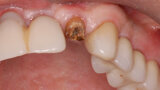

Fig. 1: The patient presented with a horizontally fractured clinical crown, an indication for a partial extraction therapy procedure.